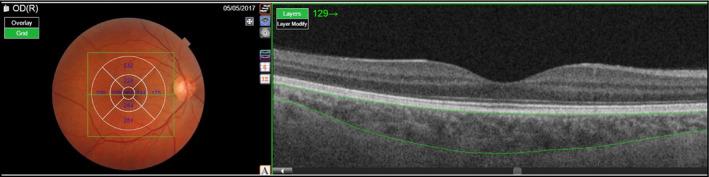

Controversy exists about the association of choroidal thickness (CTh) with blood pressure (BP) values. There is some evidence suggesting that central hemodynamics changes are associated with microvascular disease. Our study was aimed to assess the relationships between CTh and clinic and 24-h BP and between CTh and estimated 24-h aortic pulse pressure (aPP), 24-h aortic systolic BP (aSBP), and 24-h aortic augmentation index (aAIx) in a group of hypertensive patients. We enrolled 158 hypertensive subjects (mean age 48 ± 13 years) all of which underwent evaluation of the choroidal district by Swept-Source optical coherence tomography (SS-OCT) and 24-h BP monitoring, in order to measure peripheral BP and to estimate central hemodynamic parameters. Inverse significant correlations of clinic PP, 24-h aPP, 24-h aSBP, and 24-h aAIx with thicknesses of central ring, inner ring, and outer ring of the choroid and its overall average were found. The strongest of these correlations was that relating 24-h aPP with overall average choroidal thickness (r = -.531; P < .001). When we divided the study population in subjects with 24-h aPP above and below the median value (35 mm Hg), CTh were thinner in subjects with higher values of 24-aPP as compared to those with lower ones, even after adjustment for age, and other potential confounders. The relationships of CTh with 24-h aPP remained significant also taking into account the effects of various covariates in linear multiple regression analyses. Our findings support the concept of a cross-talk between macro- and microcirculation.

脉络膜厚度(CTh)与血压(BP)值之间的关联存在争议。有一些证据表明,中心血液动力学变化与微血管疾病有关。我们的研究旨在评估高血压患者组中 CTh 与临床和 24 小时 BP 之间的关系,以及 CTh 与估计的 24 小时主动脉脉搏压(aPP)、24 小时主动脉收缩压(aSBP)和 24 小时主动脉增强指数(aAIx)之间的关系。我们招募了 158 名高血压患者(平均年龄 48±13 岁),所有患者均接受 Swept-Source 光学相干断层扫描(SS-OCT)和 24 小时 BP 监测评估脉络膜区,以测量外周 BP 并估计中心血液动力学参数。临床 PP、24 小时 aPP、24 小时 aSBP 和 24 小时 aAIx 与脉络膜中央环、内环、外环及其总体平均值的厚度呈显著负相关。这些相关性中最强的是 24 小时 aPP 与脉络膜总体平均厚度的相关性(r=-.531;P<.001)。当我们将研究人群分为 24 小时 aPP 值高于和低于中位数(35mmHg)的患者时,与 24 小时 aPP 值较低的患者相比,24 小时 aPP 值较高的患者的 CTh 更薄,即使在调整年龄和其他潜在混杂因素后也是如此。在线性多元回归分析中考虑到各种协变量的影响后,CTh 与 24 小时 aPP 的关系仍然显著。我们的研究结果支持宏观和微循环之间存在交叉对话的概念。